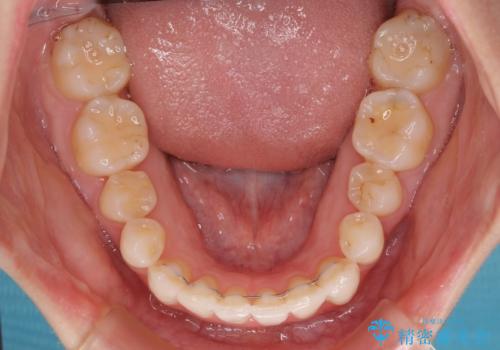

- 上下前歯のデコボコ、特に右上の八重歯を気にして来院された患者様です。

治療後半では悪阻によりマウスピースの装着時間が不十分となることもありましたが、それよりも前にしっかりと装着時間を守って治療を進めることができたため、特に気になるところなく治療を終えることができました。